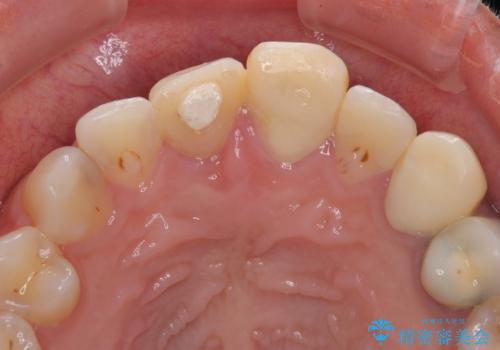

▶左上中切歯

土台を再度丁寧に整え、オールセラミッククラウンにて補綴

▶左上犬歯

根管治療行い感染除去した後、最終補綴はオールセラミッククラウンにて審美的に